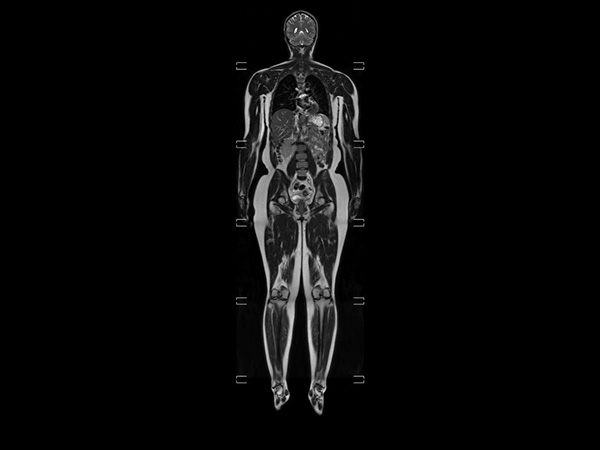

Helium-free MR operations: Wholebody imaging under 30 minutes